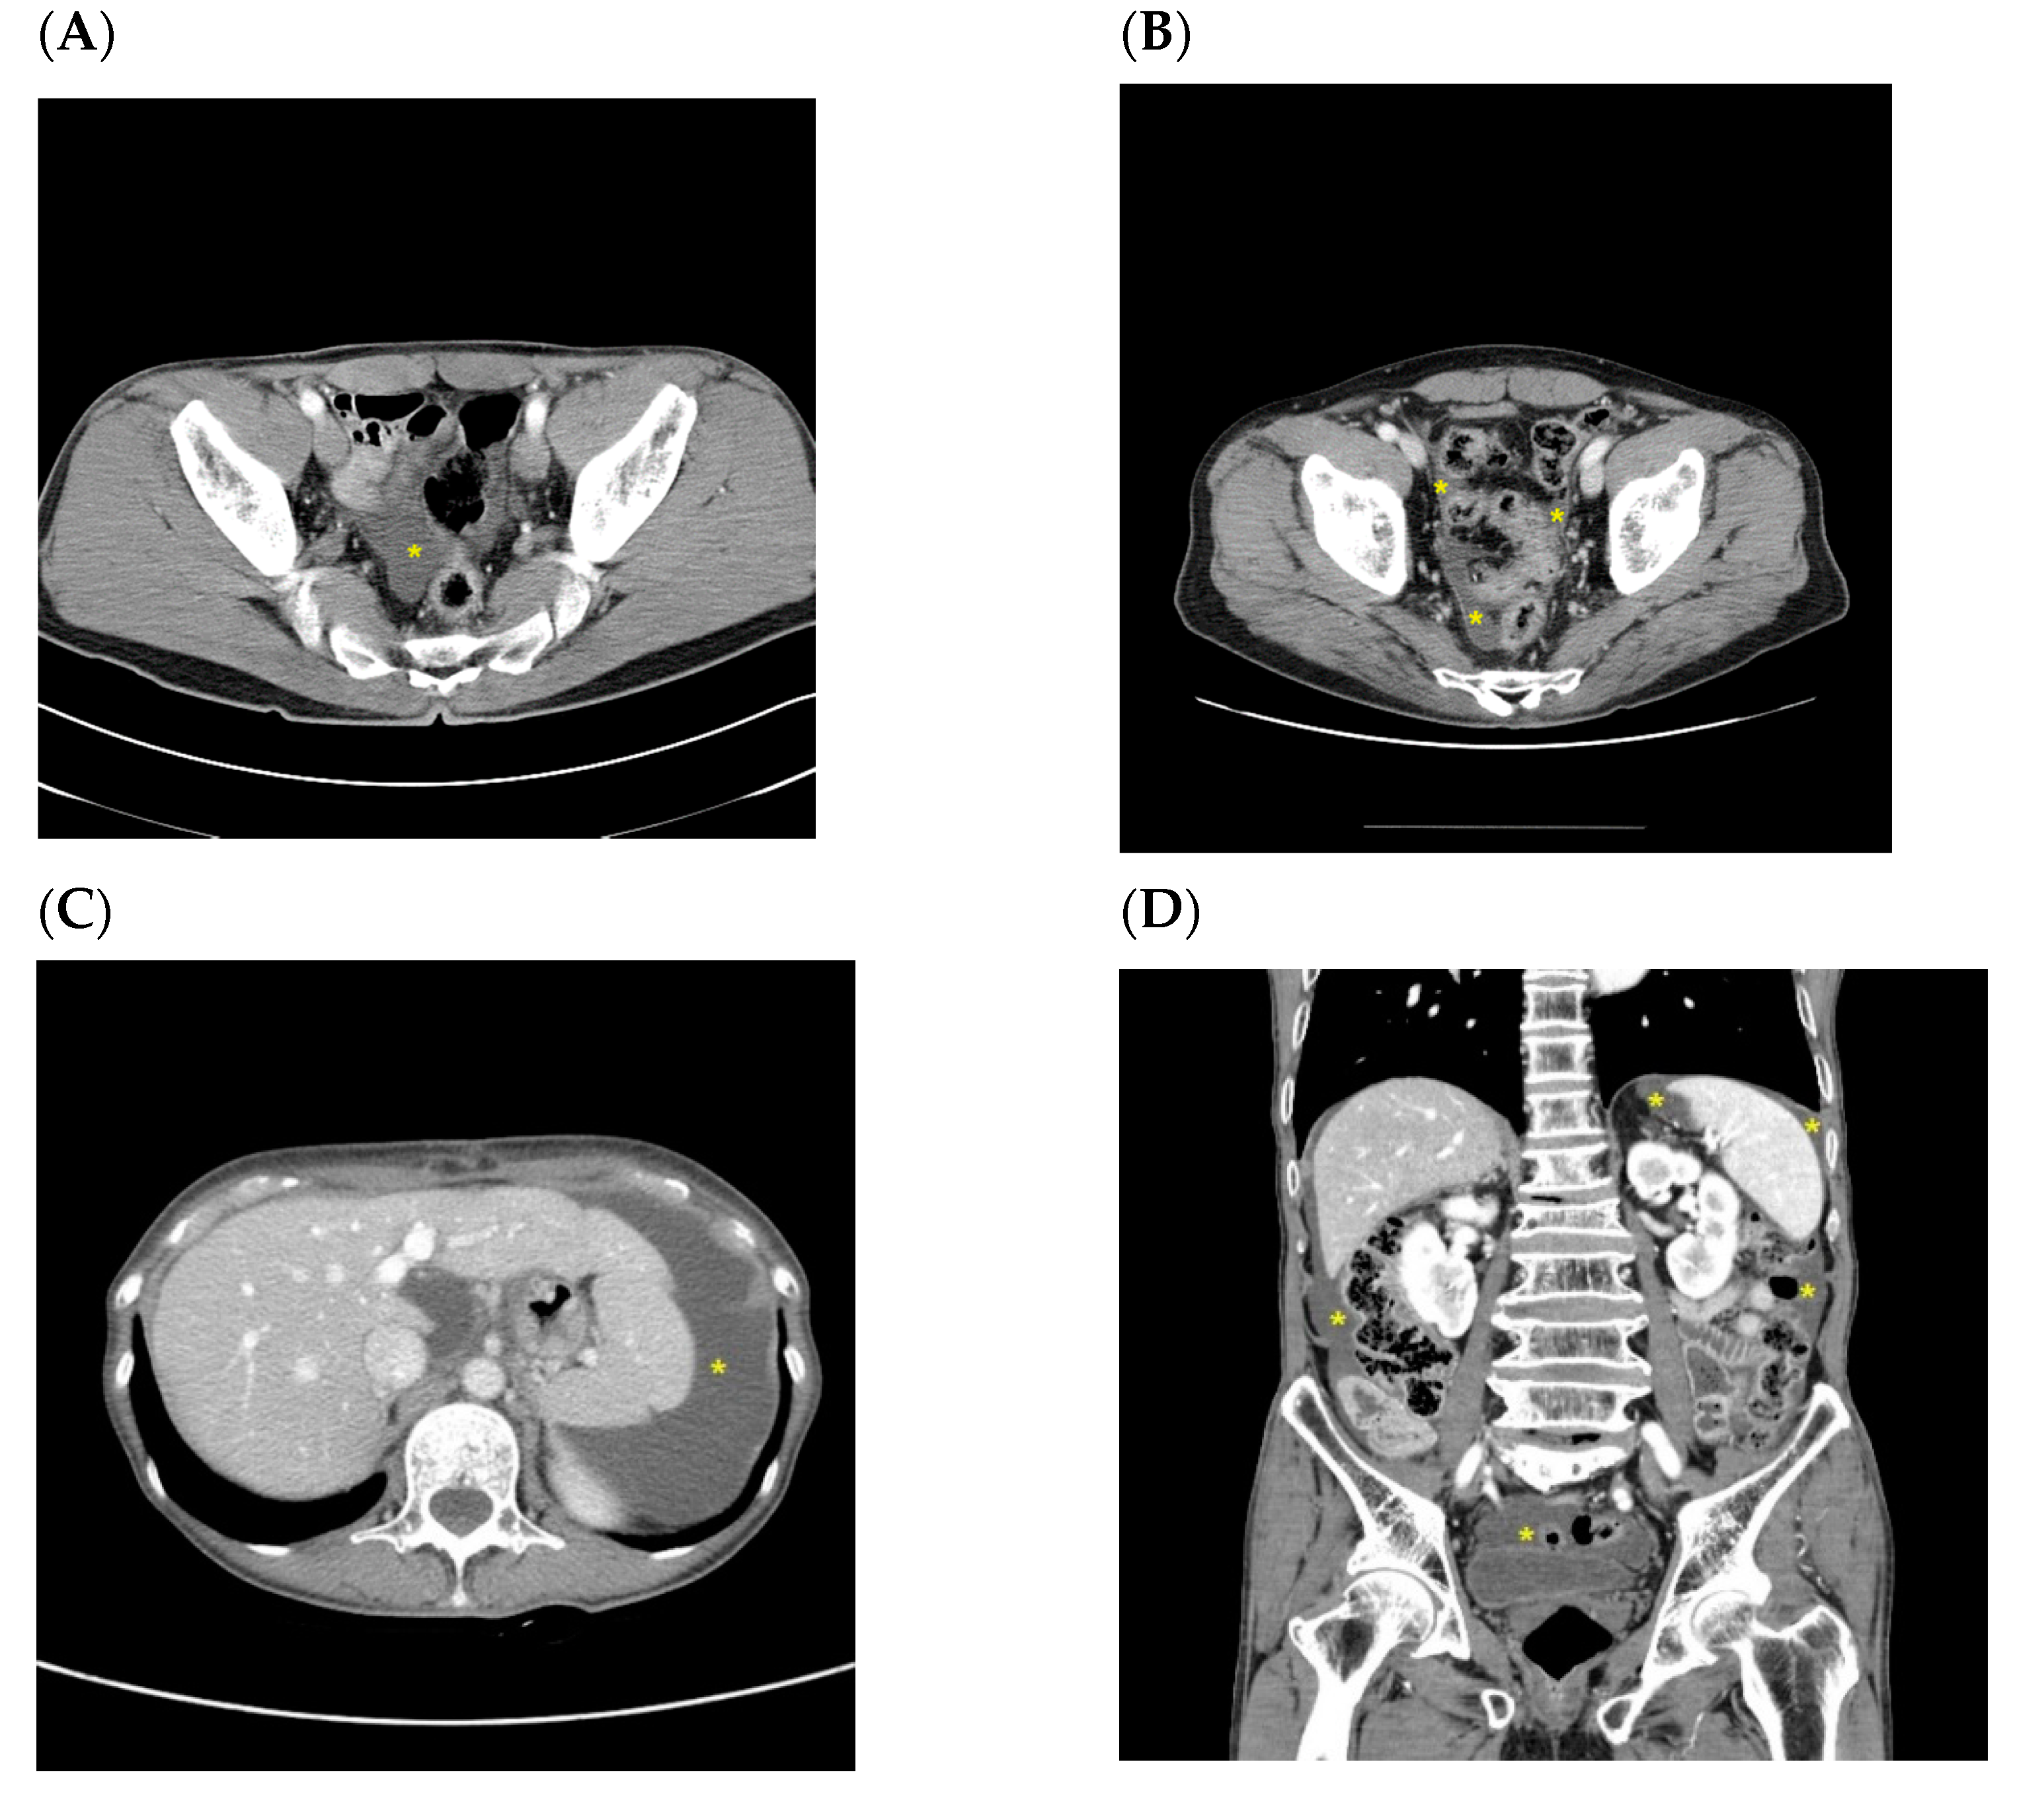

| Pt 1 | 65/M | PG | T3N3a | small pelvic cavity | Simultaneous with recurrence | T colon (increased ascites in the pelvic cavity) | 44.4 | 8.1 |

| Pt 2 | 53/F | TG | T4bN3b | small pelvic cavity | Simultaneous with recurrence | Peritoneum (increased ascites, peritoneal thickening, bowel obstruction, and Krukenberg tumors) | 18.2 | 13.2 |

| Pt 3 | 40/F | TG | T4aN3a | small pelvic cavity | Simultaneous with recurrence | Peritoneum (nodularity and increased ascites) | 73.2 | 70.3 |

| Pt 4 | 59/F | TG | T4aN3a | small pelvic cavity | Simultaneous with recurrence | Peritoneum (increased ascites and peritoneal thickening) | 25.2 | 21.7 |

| Pt 5 | 39/F | TG | T3N3b | small pelvic cavity | Simultaneous with recurrence | Peritoneum (Krukenberg tumors, nodularity, and increased ascites) | 12.1 | 9 |

| Pt 6 | 57/F | TG | T3N3a | small pelvic cavity | Simultaneous with recurrence | Peritoneum (bowel obstruction and increased ascites) | 9.8 | 4.4 |

| Pt 7 | 61/F | TG | T3N1 | small pelvic cavity | Simultaneous with recurrence | Peritoneum (increased ascites, T colon, and mesentery LNs) | 29.6 | 26 |

| Pt 8 | 68/F | PG | T4aN2 | small pelvic cavity | Simultaneous with recurrence | Peritoneum (increased ascites and peritoneal thickening) | 11.7 | 5.3 |

| A patient who first recurred with malignant ascites without other CT findings related to peritoneal seeding (later confirmed by cytology) (n = 1) | ||||||||

| Pt 9 | 49/F | TG | T3N3a | small pelvic cavity | ||||